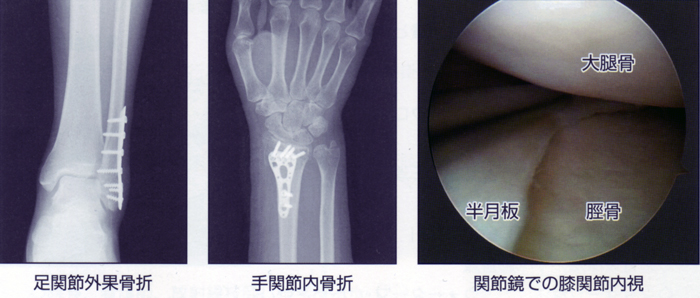

当院では患者様の機能改善、維持そして早期社会復帰を目的として適切な手術療法を行っております。当院では主に肘関節・手関節周辺骨折、膝関節・足関節周辺骨折などの外傷に対する手術や、半月板損傷や膝滑膜炎などに対する膝関節鏡視下手術を行っています。これらの手術は上肢伝達麻酔・硬膜外麻酔・局所麻酔を組み合わせた麻酔で行うため、入院を必要とせず日帰りで手術が可能です。

手術室設備として、術中患者様の全身状態を監視するモニター、酸素吸入器、応急キット、外科用イメージ装置、関節鏡ユニット、駆血帯、吸引器システムなどを配置し、前述の手術療法を安全かつ的確に行えるように備えています。